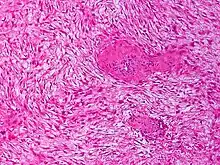

Histologically they resemble very low-grade fibrosarcomas,[5] but they are very locally aggressive and tend to recur even after complete resection. The condition is "characterized by a variable and often unpredictable clinical course."[2] There is a tendency for recurrence in the setting of prior surgery; in one study, two-thirds of patients with desmoid tumors had a history of prior abdominal surgery.[6] The condition can be chronic and may be debilitating.[7]

Similarities among bland spindle-cell lesions lead to a large number of possibilities in diagnosis, including fibroblastic sarcomas, Gardner fibroma, scar tissue or keloids, superficial fibromatosis, nodular fasciitis, myofibroma, collagenous fibroma, gastrointestinal stromal tumor, solitary fibrous tumor, and other conditions. Such conditions may therefore also be incorrectly diagnosed as desmoid tumors (29% of cases in one review).[21][15][22] Some 30–40% of desmoid tumors may be misdiagnosed.[23]